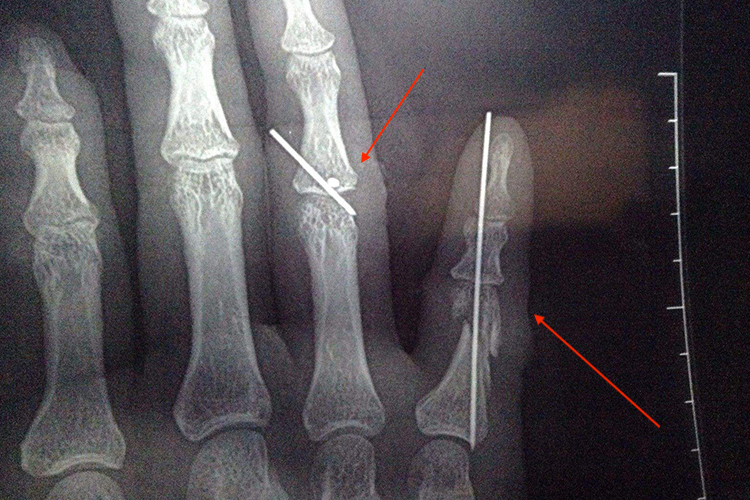

示意图

指骨骨折克氏针固定适用于近、中节的不稳定骨折的患者。方法是在复位后,在透视下经皮穿针固定,可于指骨内打入一枚克氏针,行髓内穿针固定,也可在距骨折远端的尺侧、桡侧交叉打入两枚。